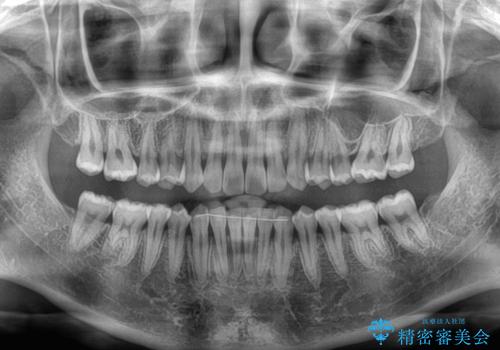

一度インビザラインのマウスピースセットをお渡しすると1年以上来院されず、マウスピースを破損したり紛失したりすると来院されるというのんびりとしたペースで治療を行ったため、4年間という長期にわたる治療となりました。

最終的には隙間は全て閉じ、綺麗な仕上がりとなりました。